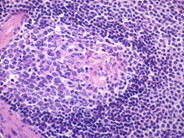

The T cell zones are architecturally similar to those of lymph nodes, with numerous interdigitating dendritic cells (IDC).